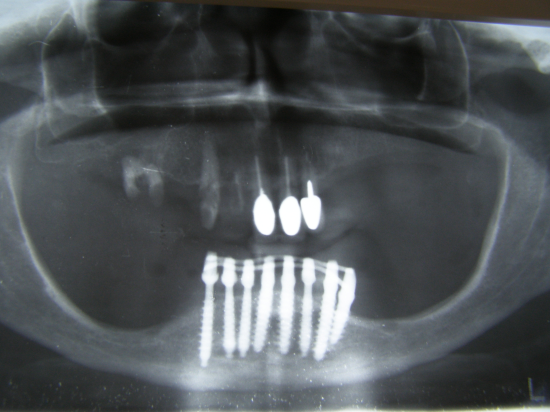

Caso Paziente 3

Donna con grave deficit osseo.Nella parte inferiore è cosi marcato che la paziente ogni qual volta esercitava pressione sulla protesi accusava dolore e parestesia(addormentamento) del viso.Cio'accadeva per la esposizione di un tratto del canale mentoniero(vedi tac) causato dal marcatissimo riassorbimento osseo dovuto anche alla protesi mobile.La paziente è stata trattata in anestesia locale in due sedute per la fase chirurgico-protesica(resina estetica) e successivamente(3 mesi dopo) finalizzata con protesi fisse in metallo-ceramica,